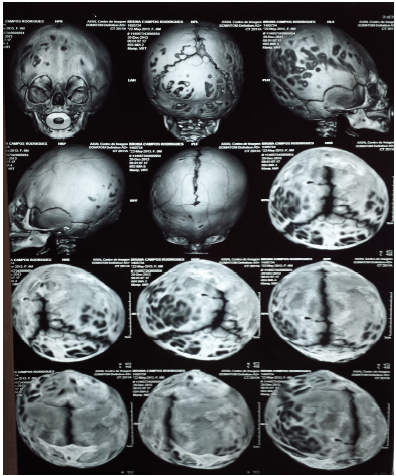

Criança de 9 meses, prematura de 30 semanas de idade gestacional, encaminhada para avaliação neurológica devido a um atraso do desenvolvimento neuropsicomotor leve. Foi solicitada uma tomografia de crânio que se vê abaixo.

A abordagem da doença detectada ao exame consiste em: